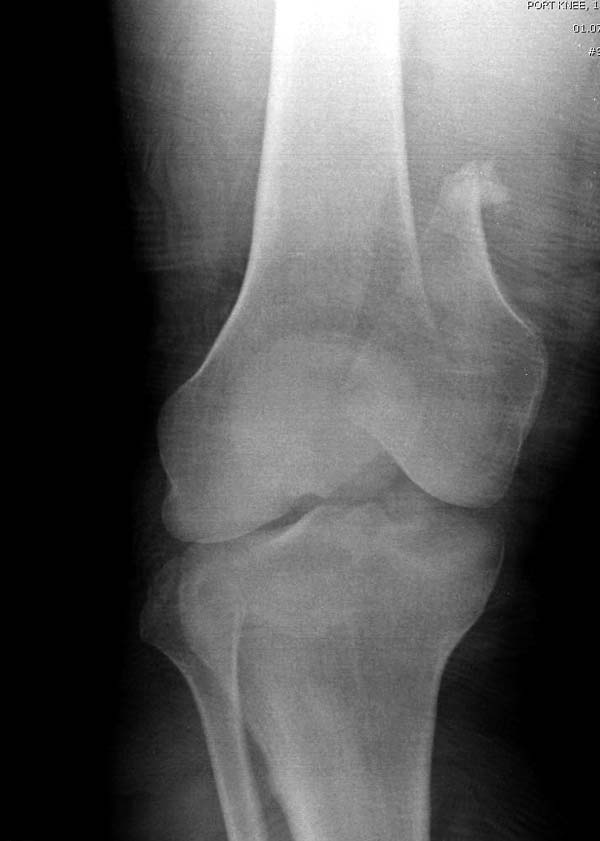

“Перелом наружного мыщелка правого бедра во фрональной плоскости был не замечен”

Диагностическая ошибка происходит, когда игнорируется правила обследования внутрисуставных переломов. Вместо полного обследования, включая КТ, ограничиваются рентгенограммой, и то в одной проекции!

Nork et al, J Orthop Trauma, 87:564, 2005 доложили, что над- и чрезмыщелковые переломы бедра в 38% имеют линию перелома в корональной плоскости!

Спасибо большое за советы! Добавляю некоторые КТ снимки. Перелом коллеги не диагностировали, видимо, расценив костную травму как повреждение задне-латерального комплекса коленного сустава. Отпишусь по результату выполненной операции.